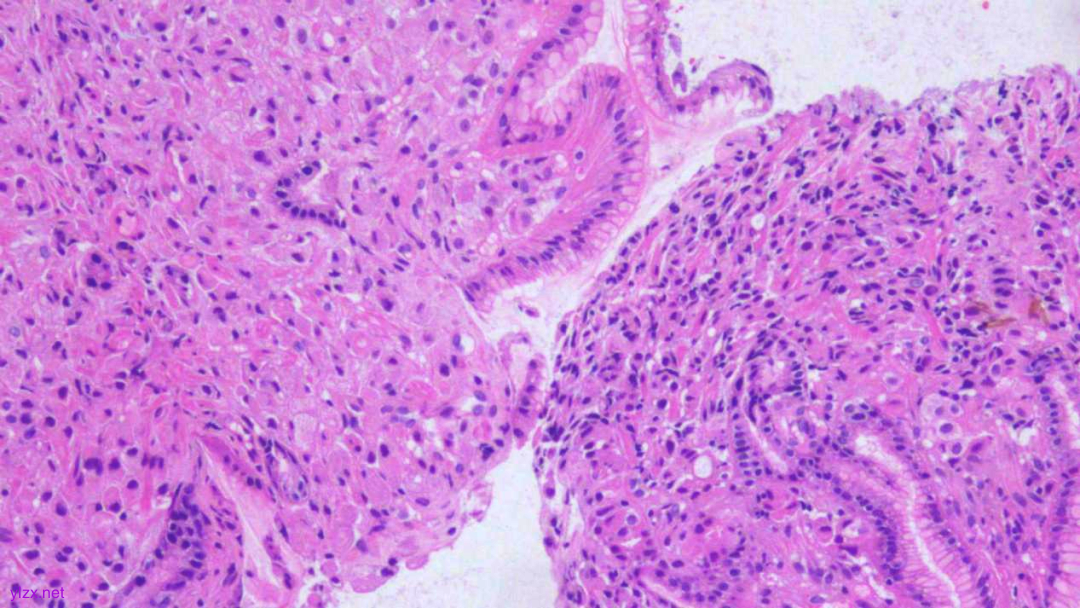

HE:

1.宫颈2点、10点:鳞状上皮下间质内见瘤组织弥漫增生,胞浆宽阔,红染,核小,较一致,部分细胞核偏位,部分细胞可见核仁;

2.宫颈5点:鳞状上皮下间质内见少量异型细胞巢,核增大,深染,浆红染,少量细胞浆内见黏液,印戒样;宫颈管搔刮组织:见血凝块、宫颈内膜组织,间质见异型细胞条索,形态同宫颈5点。

鳞状上皮下间质内见瘤组织弥漫增生,胞浆宽阔、红染,核小,较一致

瘤细胞排列偏稀疏,核小,深染,胞浆红

间质内见异型细胞巢,核增大,深染

间质内见异型细胞条索,核增大,深染,浆红

少量细胞浆内见黏液,印戒样

瘤细胞核偏位,浆红染

高倍瘤细胞见红色核仁